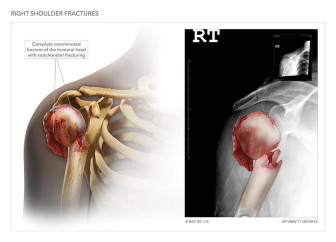

Available in high resolution JPEG or PDF formats, 8x10 print, or laminated foam core exhibit board (24x46, 30x40 or 36x48).